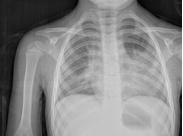

支原體肺炎(mycoplasmal pneumonia)舊稱原發性非典型肺炎、冷凝集陽性肺炎,是由支原體(mycoplasma,MP)感染引起的、基本病程間質性肺炎及毛細支氣管炎樣改變,臨床表現為頑固性劇烈咳嗽的肺部炎癥。MP是兒童時期肺炎和其它呼吸道感染的重要病原之一。本病主要通過呼吸道飛沫傳染,平時見散發病例,全年均有發病,以冬季較多。約每隔3~7年發生一次地區性流行,其流行特點為持續時間甚長,可達一年。如北京地區1990年流行自1990年1月至91年3月,持續一年二月之久。除肺炎外,還可表現為支氣管炎、氣管炎及咽炎。不少門診病人癥狀較輕,如不做血清學檢查,極易漏診。學齡兒童患病較多,學齡前兒童亦可發生,如1990年流行時北京兒童醫院3歲以下嬰幼兒病人占15%,最小一例為1歲半。痊愈后有的可攜帶病的體。